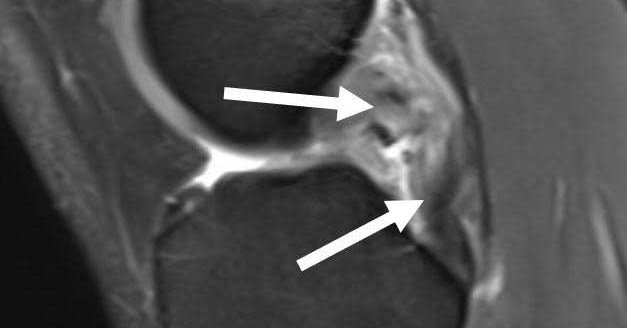

#Osteochondritis #dissecans (#OCD) of the knee is diagnosed through exam & imaging. Patients often have pinpoint joint line or kneecap pain. X-rays and #MRI help detect lesions, loose fragments, cysts, and healing potential, especially in younger patients.

Osteochondritis dissecans knee can affect any joint in the body, but the knee is the most commonly affected joint.

In this video, Dr LaPrade breaks down how to read an MRI of an osteochondritis dissecans (OCD) lesion: what to look for, how stability is assessed, and why early recognition matters for joint preservation. https://t.co/Vj8p2eipnH #medtwitter

Dr. LaPrade addresses how to read an MRI of a osteochondritis dissecans lesion, more commonly known as an OCD lesion.